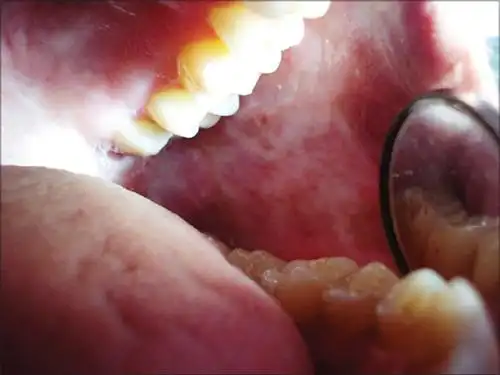

口腔癌诊断2例! - 好大夫在线